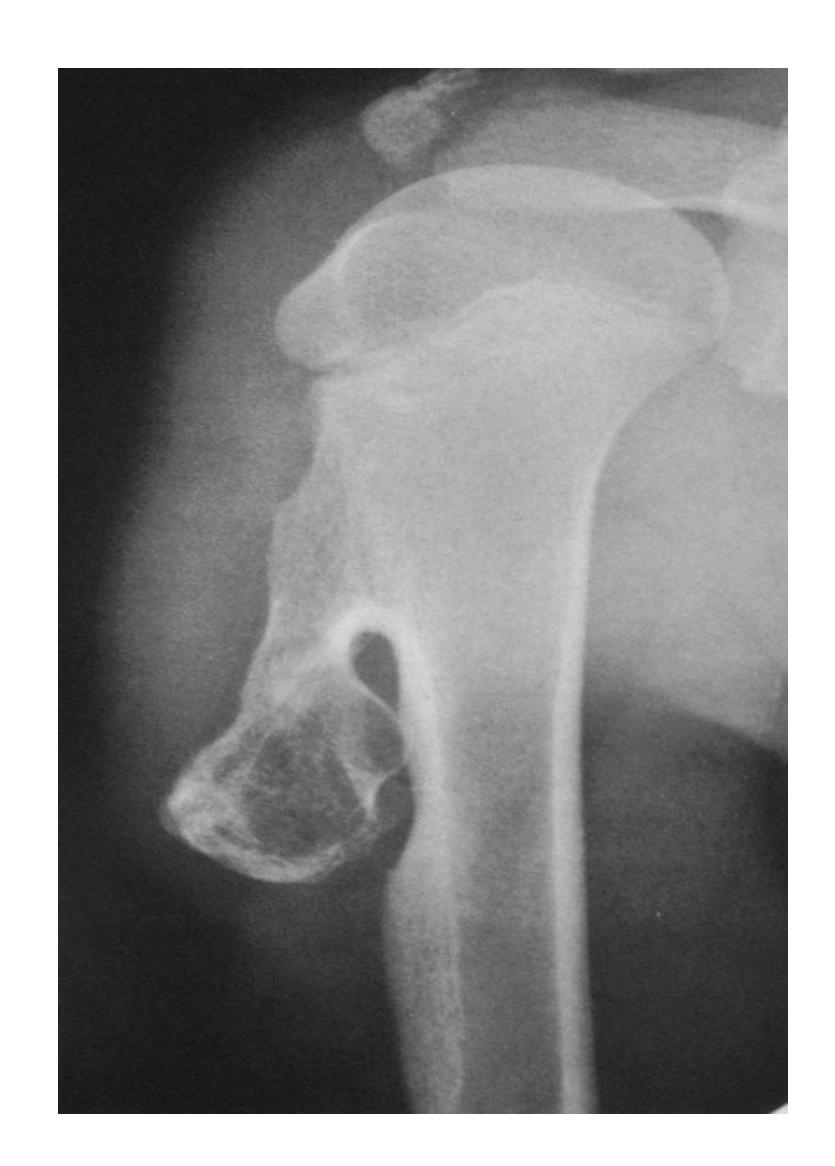

What is the diagnosis?

- X-ray showing bony tumor growing away from the epiphysis

- Diagnosis: Osteochondroma

Clinical Features:

- Pain since 2 years in proximal humerus

- Malignant transformation is rare (<1%)

- Treatment: Monitor with ESR, follow-up every 6 months-1 year

- Surgery considered if severe pain (suggesting malignant transformation)

- Surgical risk: Drop hand due to radial nerve injury